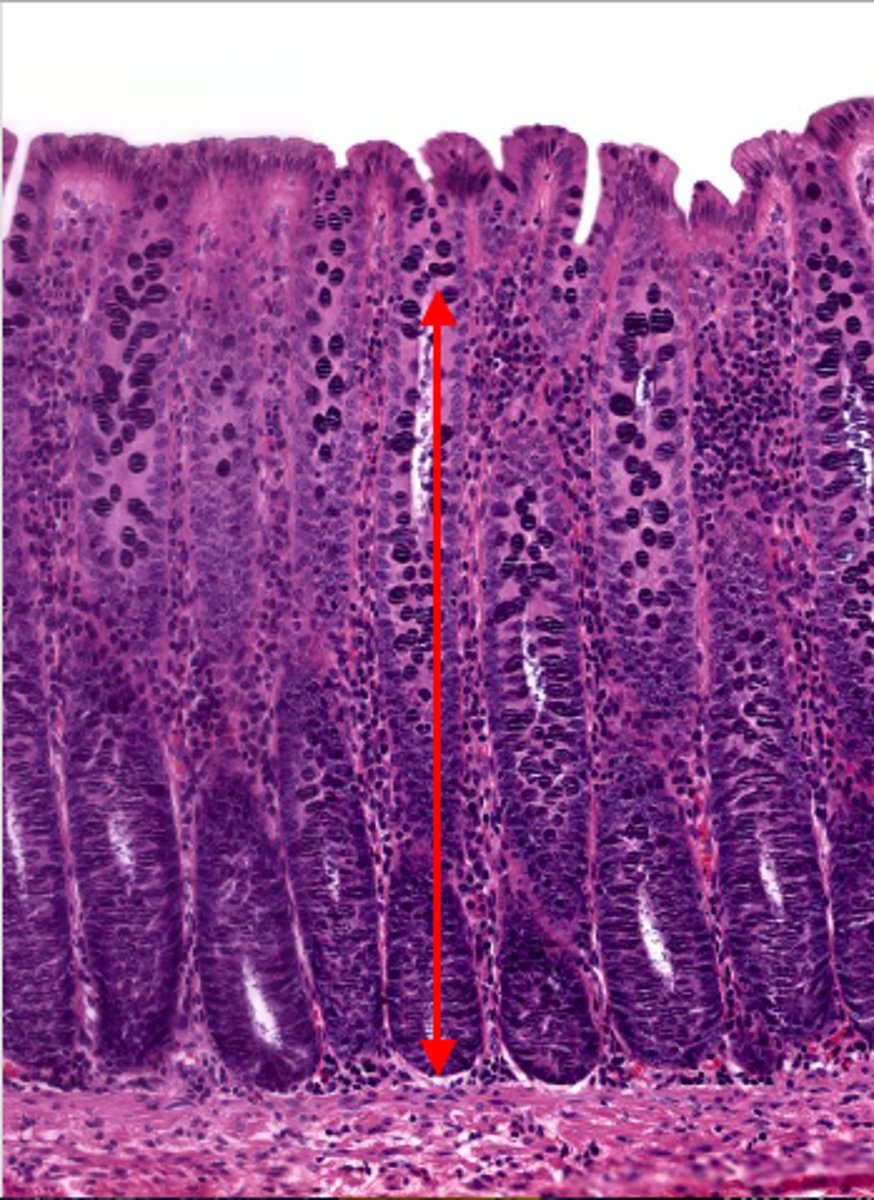

jejunum (histology)

simple columnar epithelium

what kind of epithelium lines the mucosa of the jejunum?

villi (jejunum)

intestinal crypts (jejunum)

lumen (jejunum)

mucosa (jejunum)

mucosal epithelium (jejunum)

lamina propria (jejunum)

muscularis mucosa (jejunum)

submucosa (jejunum)

contains glands and blood supply

muscularis externa (jejunum)

serosa/adventitia (jejunum)